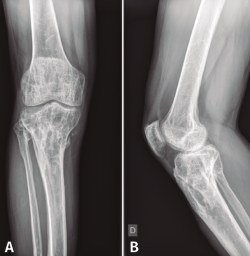

En el estudio radiológico (Figura 2) se objetiva fractura consolidada de la tibia con amplia desestructuración ósea.

Figura 2. Radiografías de frente y de perfil de tibia-peroné donde se objetiva fractura consolidada con amplia desestructuración ósea.